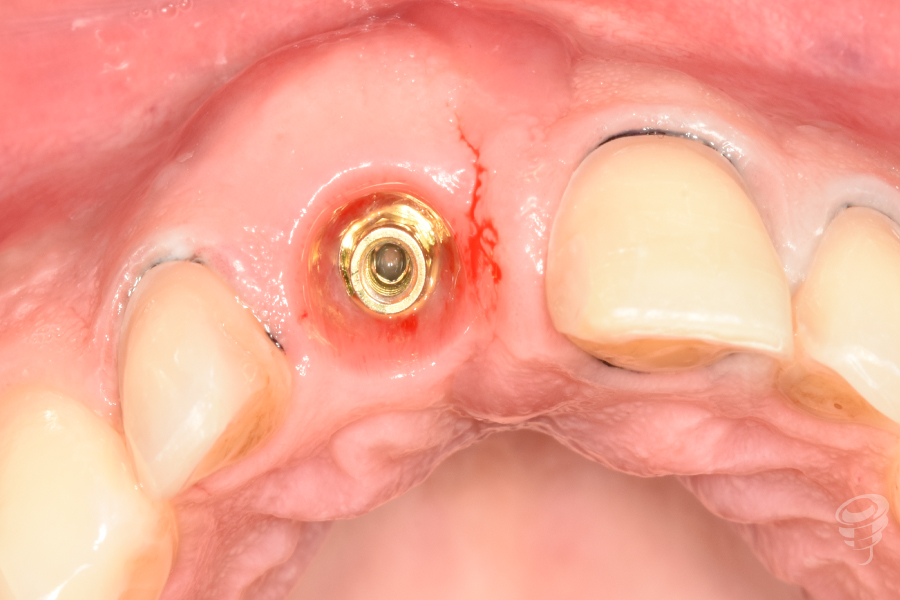

Figura 4

- Colocación del implante: Implante cónico de titanio grado IV (IPX 4012) con torque de inserción de 40 Ncm. Posición: 3mm apical al CEN del diente adyacente, 2mm palatino a la tabla vestibular.